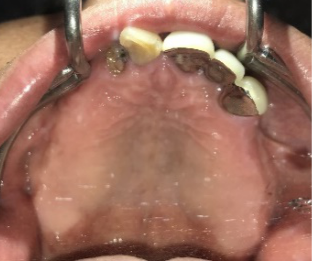

女性Mさん 40代(インプラント)

主訴

下、左右歯がないところに歯を入れたい。

治療内容

右下に2本、左下に1本インプラントを入れました。

所感

下顎左右奥の歯がないところに、インプラント治療を希望されて来院されました。X-Guideを使用し埋入しました。治療後「左右の奥歯でしっかり噛めてうれしいです。」と、とても喜んでくださいました。

インプラント3本:¥363,000×3本=¥1,089,000(税込)

Before

After